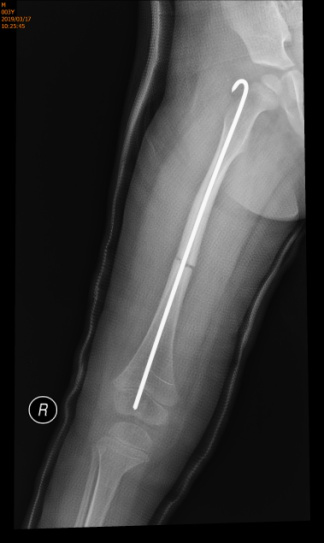

我科收治后,积极组织科室讨论治疗方案。考虑到患儿出生后长期卧床、不能行走,骨折疏松严重,不能采取常规手术方案。同时也要防止远期再次骨折的发生,最后决定采用髓内Rush钉固定,既保证了骨折的良好复位,又能降低远期再次骨折的发生。确定了手术方案后,我科积极联系麻醉科、小儿重症医学科等科室充分评估患儿术中、术后风险,保证患儿安全度过手术、平稳回到病房。

经过前期充分准备,手术进行非常顺利,术中患儿各项生命指标平稳。手术后平稳转入小儿重症医学科。术后第二日平稳回到我科。经我科室的积极诊治及相关科室的密切配合,患儿平平安安出院。患儿家长对我科室的治疗十分满意,给予了充分肯定和赞扬。

术后复查骨折对位好,Rush钉位置好